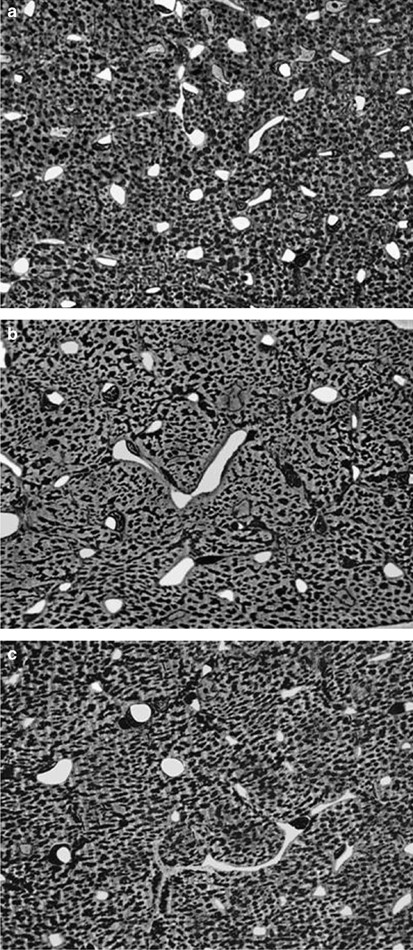

Figure 1 shows that the number of capillary profiles per area myocardium is markedly lower in Fgf2+/− (Figure 1b) and Fgf2−/− (Figure 1c) mice compared to wild-type animals (Figure 1a). Figure 2 indicates that three-dimensional myocardial capillary supply (assessed as capillary length density (LV), that is, capillary length per volume myocardium) was significantly lower in Fgf2+/− (3228±245?mm/mm3) and Fgf2−/− mice (3385±241?mm/mm3), respectively, than in Fgf2+/+ littermates (4403±290?mm/mm3, P<0.05, Figures 1 and 2). There were no differences in capillary length density between male and female animals of the same genotype.

Reduced myocardial capillarization in Fgf2+/− and Fgf2−/− mice. (a–c) Light microscopical aspect of myocardial capillary supply in wild-type (a), Fgf2+/− (b), and Fgf2−/− (c) mice. The number of capillary profiles (white structures) per area myocardium is markedly lower in Fgf2+/− (b) and Fgf2−/− (c) mice compared to wild-type mice (a). Semithin section, magnification: 1:500.